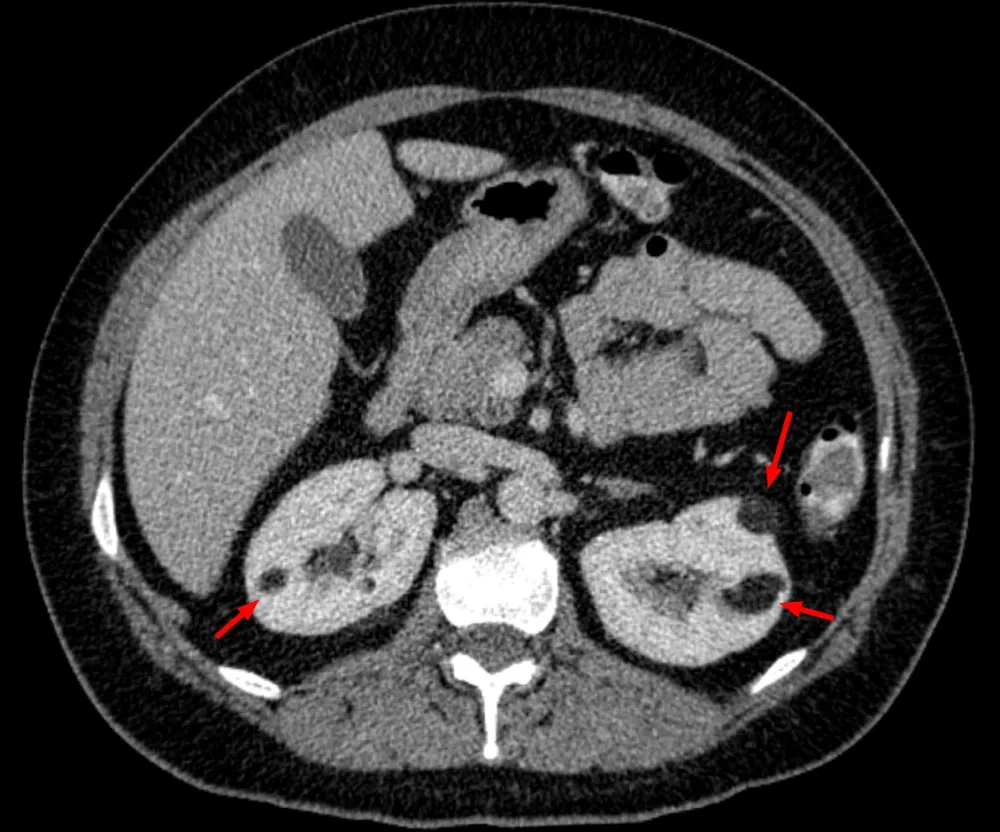

* Pacientes com **AML múltiplos (≥3), bilaterais e/ou grandes(ou seja, ≥4 cm)** têm maior probabilidade de ter CET (imagem abaixo).

* Nestes pacientes é essencial realizamos uma avaliação completa para CET, que inclui avaliação clínica, critérios diagnósticos e até testes genéticos).

TC abdome sem contraste evidenciando imagens hipodensas na região cortical de ambos os rins